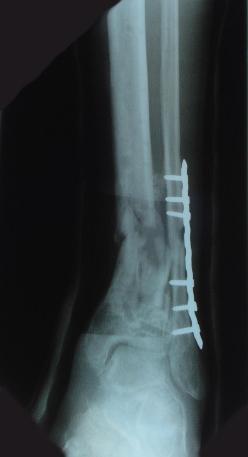

Post-corrective surgery X-Rays of the damaged right & left legs / ankles

The first two x-rays show Liam’s left ankle and pelvis prior to the accident. For comparison purposes it is interesting to see the

differences. The next x-rays were taken after the corrective surgery performed by Dr. Armendariz. Noticed that Dr. Armendariz has used tibia

bracing and also aligned the bone fragments of the left leg so that they could heal in the proper orientation. The external fixation has been

removed and Liam’s left foot has been returned to a more natural alignment.